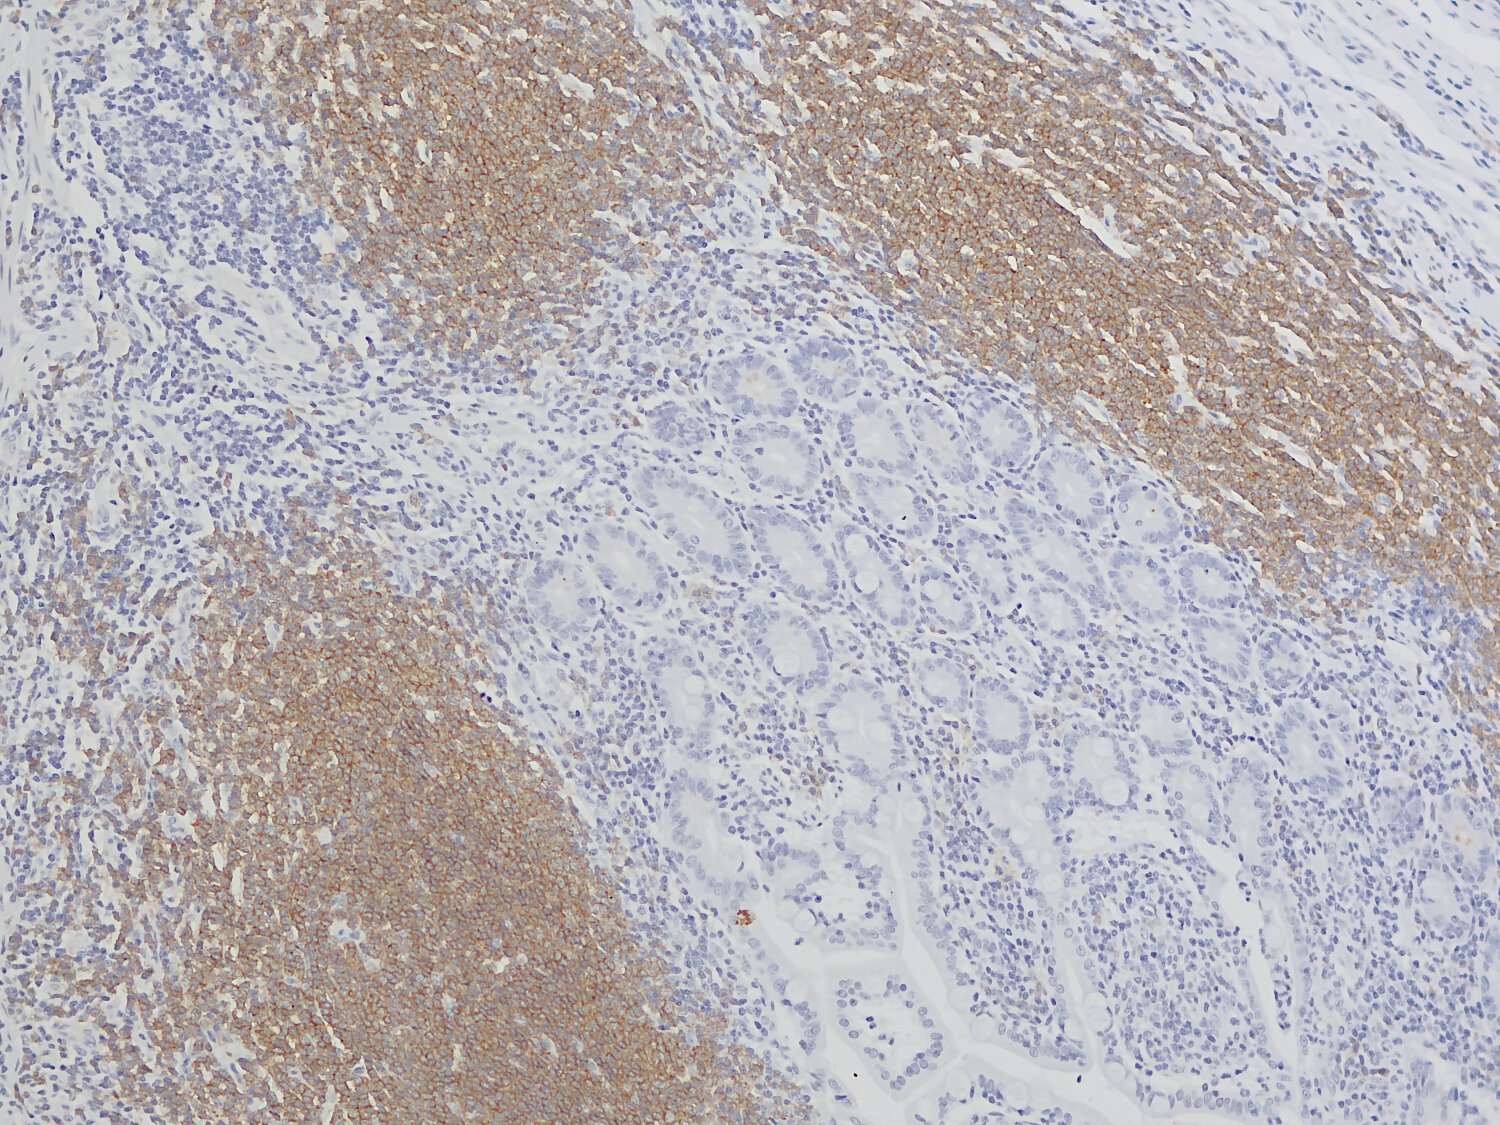

IHC-P: 1 : 4000 gallery

Immunohistochemistry (IHC-P) of formalin fixed, paraffin embedded (FFPE) tissue (some antibodies require special antigen retrieval steps, please refer to the ”Remarks” section). Immunoreactivity is usually revealed by fluorescence or a chromogenic substrate.

Immunofluorescence image of a human FFPE tonsil section stained for CD19 (B cells, red) and CD3e (T cells, green)